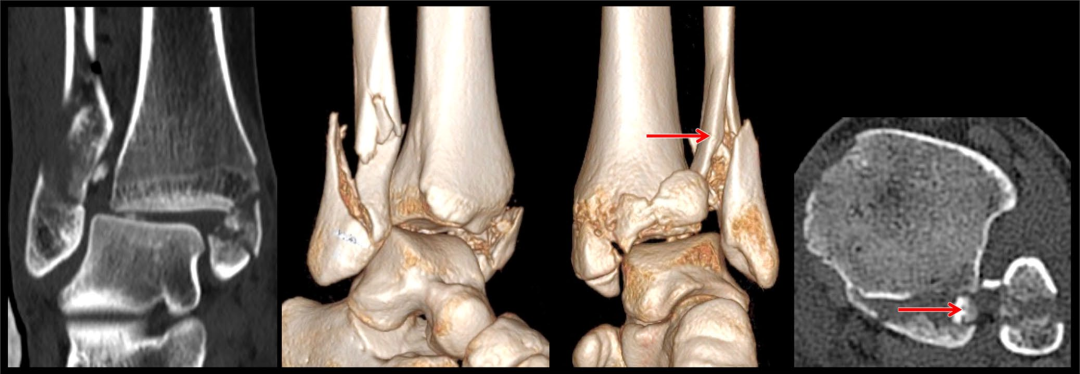

影像金标准: CT+3D重建

首先通过X线片、CT明确骨折类型及骨折细节,此例腓骨骨折属于WeberB型,通过CT发现内侧间隙增大,考虑三角韧带损伤的可能较大,同时后踝骨折块较小。

作者选择后外侧入路,先复位腓骨,后踝未予处理,未予三角韧带修补,复位腓骨后检查下胫腓间隙不稳定行下胫腓螺钉固定。术后CT可见下胫腓间隙复位可。作者术中通过复位外踝、下胫腓间隙后透视见内踝间隙匹配可。